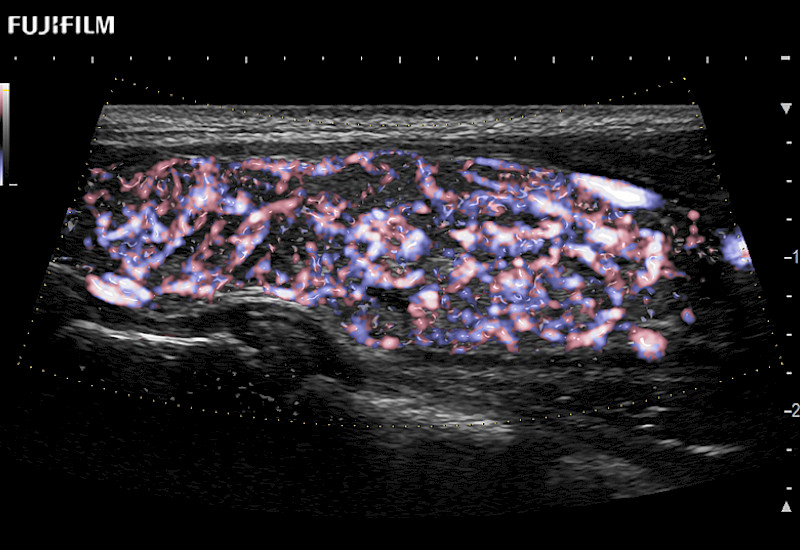

Learn moreFujifilm Healthcare continues to listen to the experts, our neurosurgeons, by developing an ultrasound system specifically designed for the Operating Room.

Guidance is the fundamental purpose for all of our surgical ultrasound technology. Fujifilm Healthcare is committed to designing tools that help neurosurgeons navigate inside the human body and provide the necessary information to immediately make critical surgical decisions.

With the ARIETTA Precision the next level of surgical ultrasound is here.